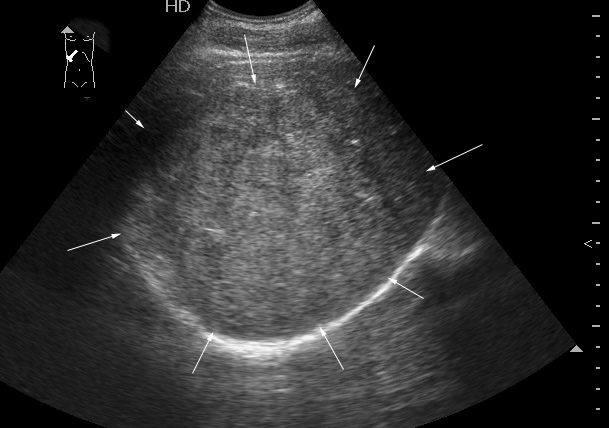

Молодой человек, наркоман, поступил в хирургическое отделение с подозрением на абсцесс печени.

Жалобы на высокую температуру, слабость.

Сонограмма печени:

Год назад при УЗИ в печени находили образование больших размеров.

Что-то не укладывается именно ультразвуковая картирка в абсцесс печени.

на узи на абсцесс не похоже, образование солидное ----гепатома?

Гигантская капилярная гемангиома печени.